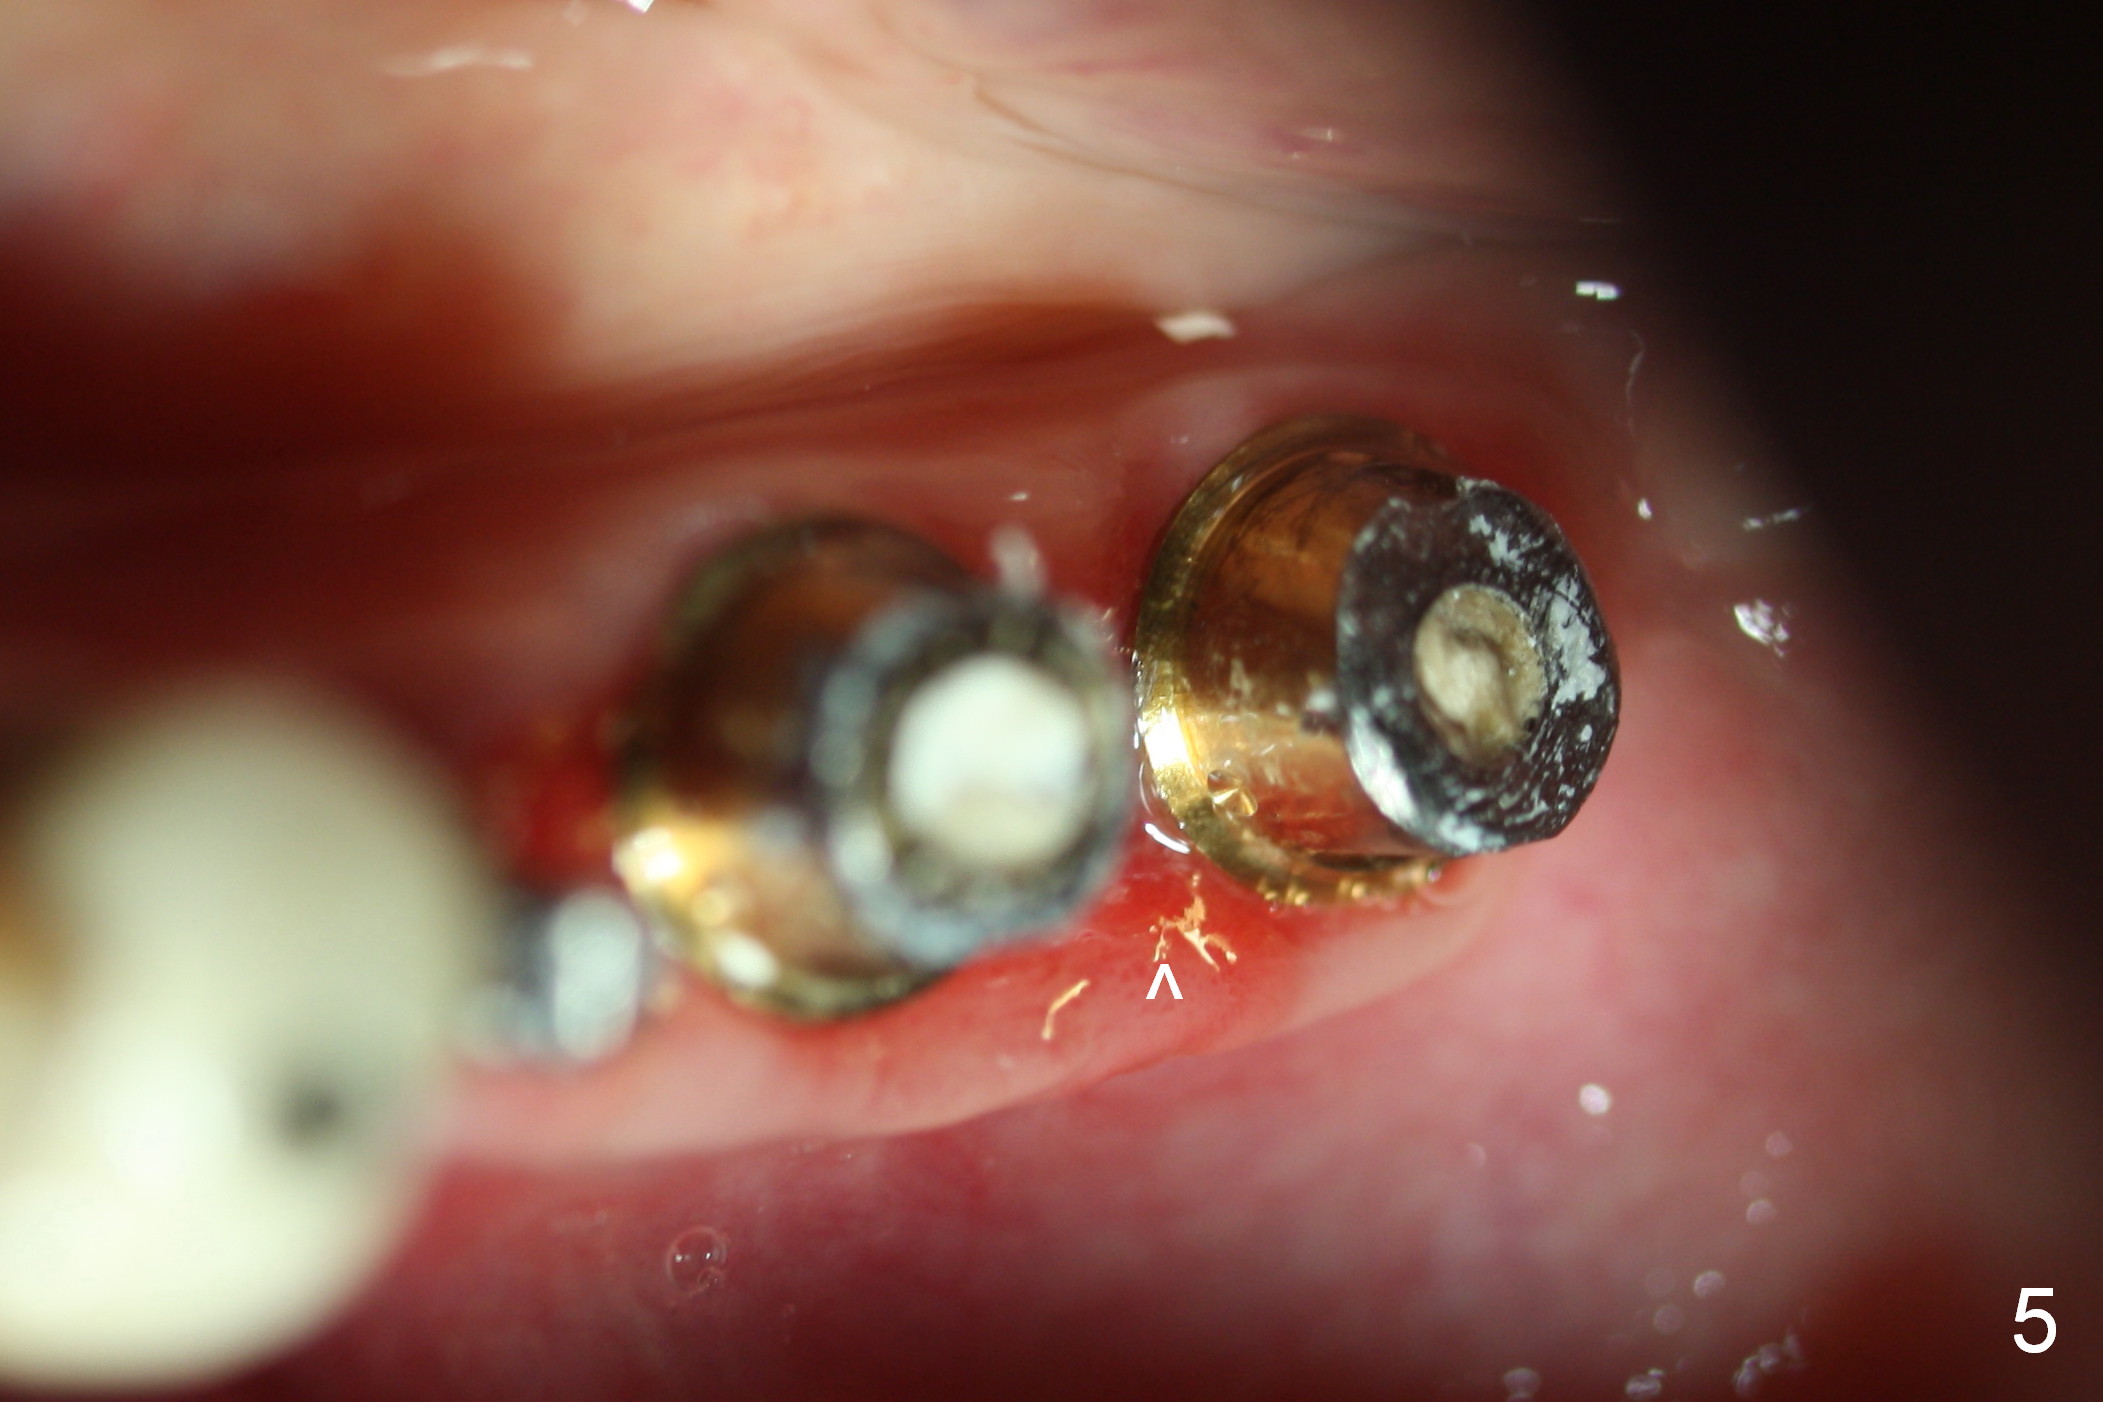

The patient is doing well postop, but 1 month postop, she complains of pain in the left submandibular area. When the immediate provisional is removed, the gingiva between the implants is erythematous (Fig.5 ^). The provisional is modified with accentuated grooves between the margins of the implants (Fig.6 *) with oral hygiene instruction. In fact the provisional is not cemented so that it is easy for self cleansing. There is crestal bone resorption 3 months postop (Fig.7,8). No further bone loss 1 year post cementation (Fig.9, cropped from pan). The bone density around the implants increases 2 years 8 months post cementation (Fig.10).